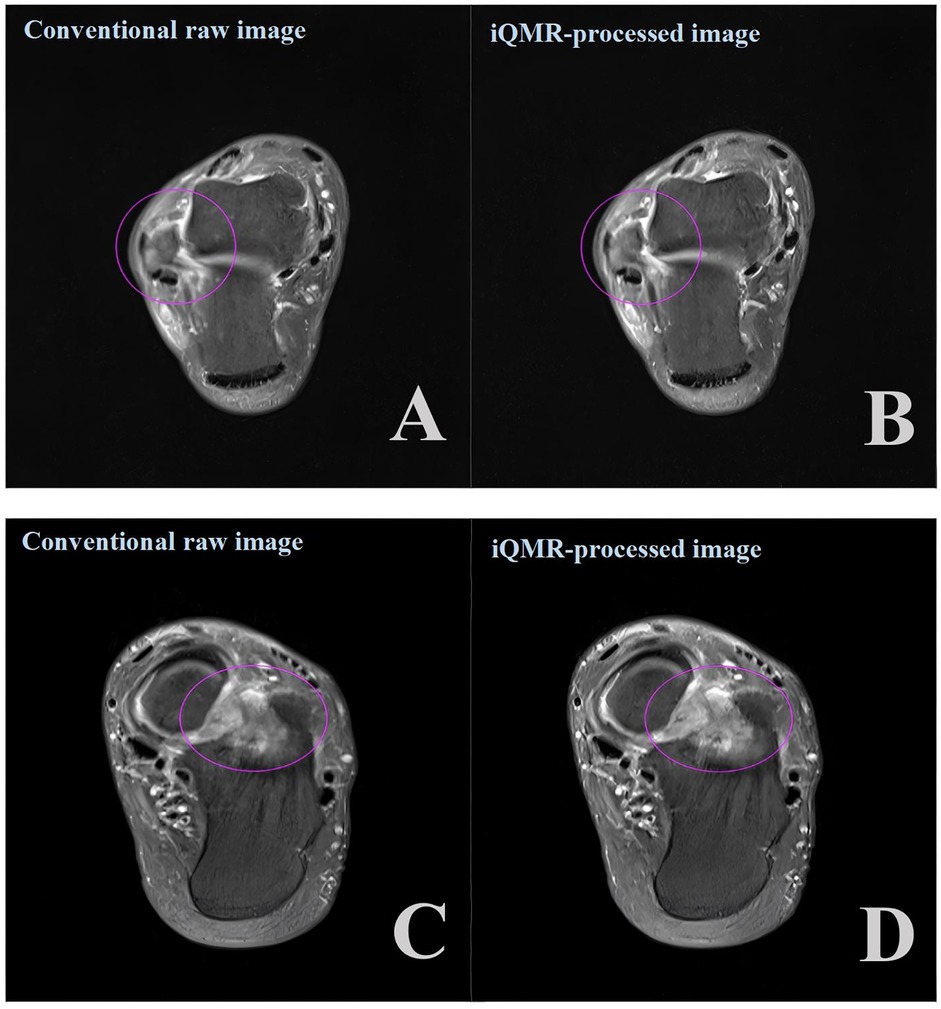

The diagnostic accuracy of the four groups of PDWI-FS images for structural injuries of tendons and ligaments was not significantly different (P > 0.05, Figures 6A–D). The Kappa of 0.919 (CI: 0.971–0.866)showed a high degree of inter-observer agreement in grading between the two musculoskeletal radiologists.

Figure 6

Side-by-side comparison of MRI images. The top row shows a conventional raw image (A) and its iQMR-processed counterpart (B) with a purple circled area. The bottom row repeats this format, with the raw image (C) and the processed image (D) also displaying a purple circled area. Both processed images appear sharper than their raw counterparts.

Figure 6. Axial proton density-weighted imaging with fat suppression (PDWI-FS) demonstrating: (A,B) ligament injuries (purple circles) using conventional and iQMR protocol; (C,D) bone marrow edema (purple circles) using conventional and iQMR protocol. iQMR, intelligent quick magnetic resonance.